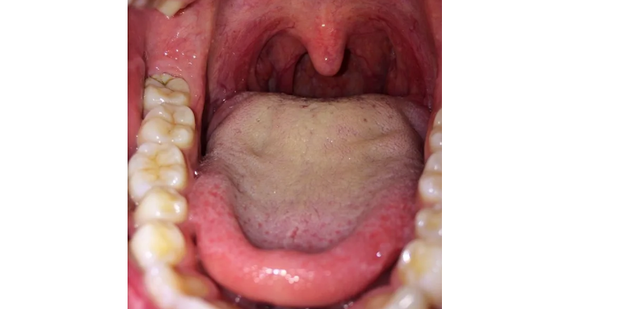

扁桃体肿大怎么办呢?今天就教大家如何操作使用方法步骤。

1:扁桃体肿大怎么办?可以用药物治疗,严重的需要手术切除。

2:第一个选项就是药物治疗,抗菌和抗炎药物治疗。这种局部治疗方法的缺点是,它只能减少炎症,但不能清除扁桃体隐窝中的细菌。一旦身体抵抗力降低,很容易反复发作,并随着时间来自的推移形成慢性病变。

3:手术治疗:扁桃体切除术的适应性包括扁桃体切除术引起上呼吸道阻塞,导致严重打鼾、吞咽困难、发音不清等;有一个或多个扁桃体脓肿;扁桃体引起全身性疾病,并成为局部扁桃体。